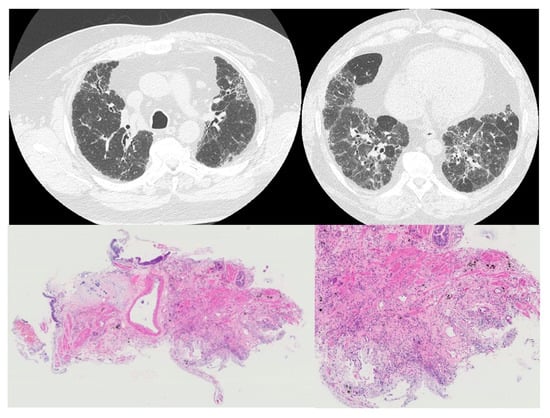

The Characteristic of Transbronchial Lung Cryobiopsy in the Pathological Diagnosis of Hypersensitivity Pneumonitis

2.3. Evaluation of HRCT Findings Based on HP Diagnostic Guideline

2.4. Pathological Diagnosis

3.2. Radiological Findings and Diagnosis

3.3. Pathological Findings and Diagnosis